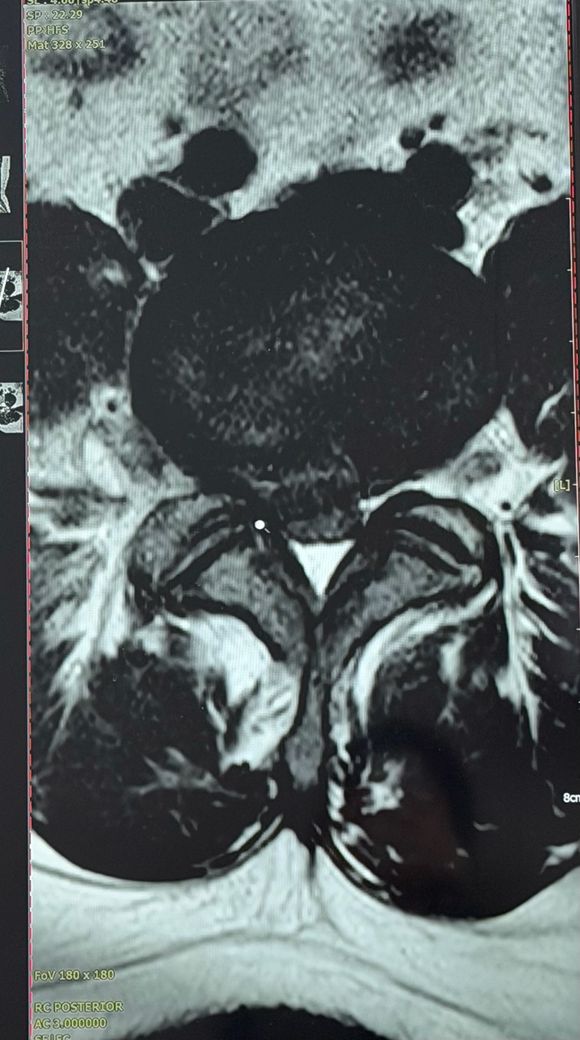

병원에서는 디스크가 터져서 수술을 바로 해야한다고 하셨는데 주변에서 젊은 나이에 수술은 아니라면서 만류하더라고요 ㅜㅜ 그래서 혹시나 조언을 얻고자 글을 남깁니다 mri 사진도 첨부합니다

이미지상으로 볼 때, 요추 4-5번(L4-5) 혹은 요추 5번-천추 1번(L5-S1) 부위의 디스크 탈출증(Disc Herniation)이 매우 심한 상태로 보입니다.

-대형 탈출: 디스크 수핵이 터져 나와 신경관(Spinal Canal)의 상당 부분을 점유하고 있습니다.

-신경 압박: 신경이 지나가는 통로가 매우 좁아져 있으며, 이로 인해 우측 다리로 내려가는 신경이 강하게 눌리고 있는 상황입니다.

• 주변에서 하는 이야기와 전문가가 하는 이야기 중 무엇을 더 신뢰하실지 잘 생각해보시길 바랍니다. 올리신 사진의 소견만으로 평가를 하는 것은 제한적이긴 하나 디스크 돌출이 명확하며 척수 신경이 눌린 것도 상당히 심해 보입니다. 병원에서 수술을 권유할만한 근거가 충분히 있어 보이긴 합니다. 대신 선택을 해드릴 수는 없는 만큼 이것저것 고려하여서 현명한 선택을 하시길 바랍니다.

• 제공하신 MRI(요추 시상면)와 증상 설명을 종합하면, “디스크가 터졌다”는 표현은 요추 추간판 탈출증 중에서도 탈출(extrusion) 또는 유리(sequestration)에 가까운 형태가 의심됩니다. 다만, 이 소견이 곧바로 수술의 절대 적응증을 의미하는 것은 아닙니다.